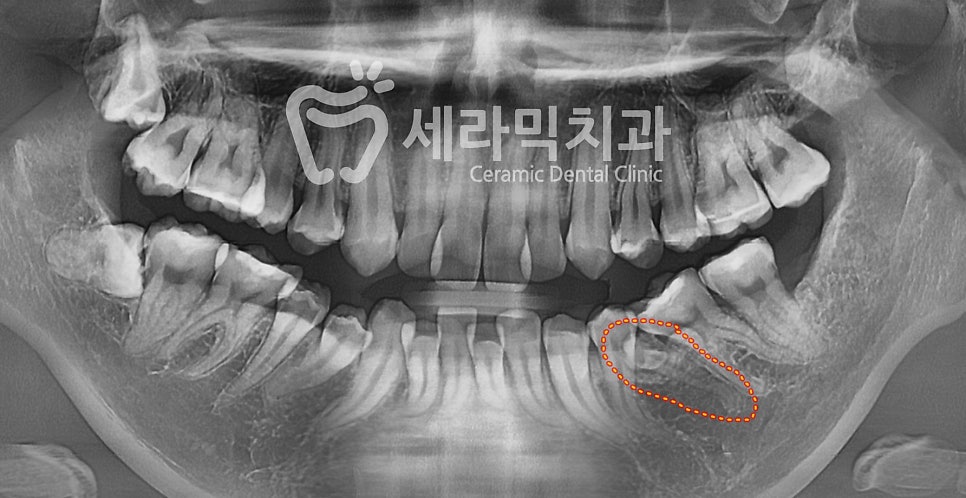

④ #35 치아가 매복되어 있음

(아래 사진을 보시면 붉은 원 안에 35번 치아가 숨어 있습니다.)

① 치아배열과 돌출 개선을 위해 발치 교정을 진행합니다.

#14, 24, 35(매복치), 44를 발치하고 위, 아래에 교정장치를 부착합니다.